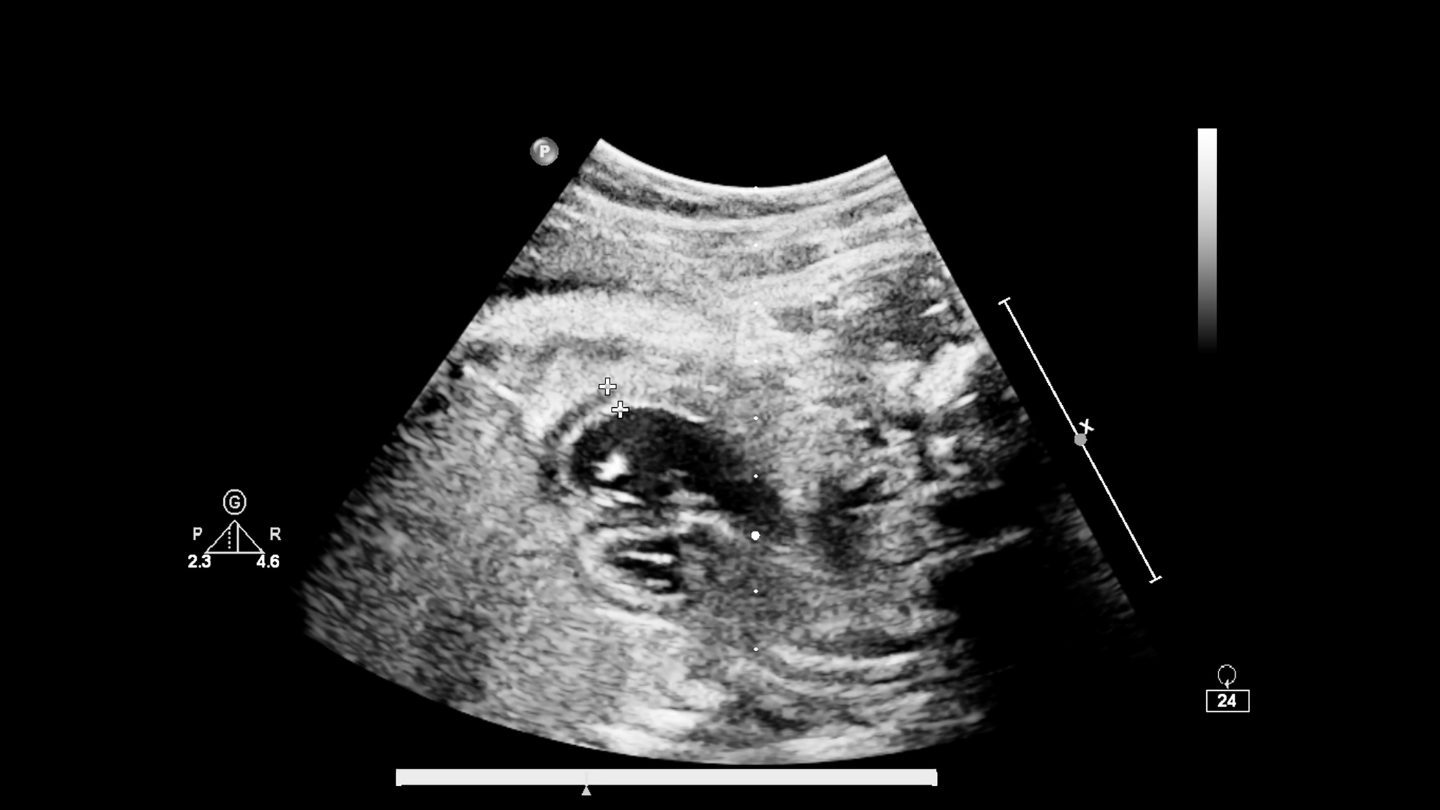

Siêu âm đầu dò âm đạo là phương pháp sử dụng một đầu dò nhỏ (khoảng 2 - 3 inch) đưa nhẹ nhàng vào âm đạo để quan sát chi tiết:

Khác với siêu âm bụng (đặt đầu dò ngoài da), siêu âm đầu dò cho hình ảnh rõ nét hơn ở giai đoạn thai sớm hoặc khi đánh giá bệnh lý phụ khoa. Siêu âm đầu dò là phương pháp quan trọng để:

- Phát hiện thai sớm (6 - 8 tuần);

- Chẩn đoán thai ngoài tử cung;

- Phát hiện u nang buồng trứng, u xơ tử cung;

- Đánh giá độ dày nội mạc tử cung.